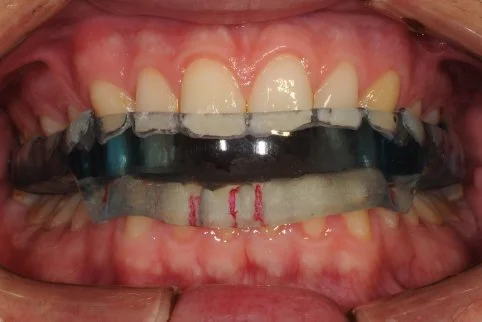

A TMJ Disorder patient requires conservative management with “Full Occlusal Therapy” in 3 stages along with concurrent Full Counselling (refer to journal papers 19 and 20).  In other words, we need to get the disc back into the centre of the joint where it belongs starting with Full Counselling and then a Fully Protective Occlusal Splint (Stage 1).  This splint is made of acrylic resin (used for dentures) and can be made in clear resin but is usually coloured blue or pink to hide any future discolouration (as in the photos below). The splint usually fits the upper teeth and only one is required.

Stage 1 - Fully Protective Occlusal Splint - 4 SA’s over a 3 month period